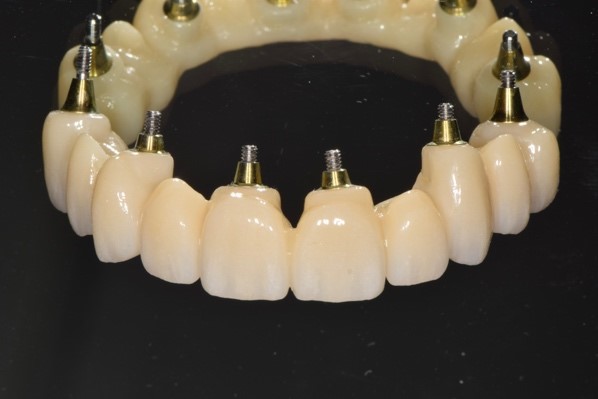

Il laboratorio odontotecnico utilizzava le più recenti tecnologie CAD/CAM per produrre una protesi dentale personalizzata e di alta qualità che si adattasse perfettamente e garantisse funzionalità ed estetica ottimali. Il concetto iPhysio® facilita il recupero automatico del profilo di emergenza sottogengivale da parte dell'odontotecnico per la realizzazione di soluzioni personalizzate sia con la protesi cementata che con la protesi avvitata (Fig. 5 a,b,c). La paziente tornava per il posizionamento del restauro finale in zirconio avvitato (Fig. 6 a,b).

Profili di emergenza ideali disegnati dagli iPhysio

Fig. 5(a)

Profili di emergenza ideali disegnati dagli iPhysio 2

Fig. 5(b)

Profili di emergenza ideali disegnati dagli iPhysio 3

Fig. 5(c) Profili di emergenza ideali disegnati dagli iPhysio®.